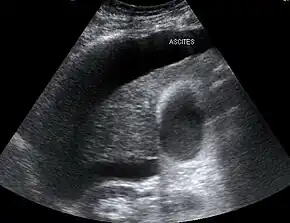

Those affected usually have cirrhosis, though it may also occur in alcoholic hepatitis or liver failure.[1] Additional risk factors include low blood pressure and low sodium.[1] Onset may be triggered by infection, gastrointestinal bleeding, overuse of diuretics, draining ascites (fluid in the abdomen), surgery, or medications like ACE inhibitors.[1][2] The underlying mechanism involves liver problems precipitating insufficient blood flow to the kidneys.[1] The kidneys are otherwise normal.[2] Diagnosis is based on laboratory tests of kidney function, after ruling out other possible causes.[2] Type 1 includes a rapid decline in kidney function, while type 2 is associated with ascites that does not improve with diuretics.[2]

Both types of hepatorenal syndrome share three major components: altered liver function, abnormalities in circulation, and kidney failure. As these phenomena may not necessarily produce symptoms until late in their course, individuals with hepatorenal syndrome are typically diagnosed with the condition on the basis of altered laboratory tests. Most people who develop HRS have cirrhosis, and may have signs and symptoms of the same, which can include jaundice, altered mental status, evidence of decreased nutrition, and the presence of ascites.[6] Specifically, the production of ascites that is resistant to the use of diuretic medications is characteristic of type 2 HRS. Oliguria, which is a decrease in urine volume, may occur as a consequence of kidney failure; however, some individuals with HRS continue to produce a normal amount of urine.[7] As these signs and symptoms may not necessarily occur in HRS, they are not included in the major and minor criteria for making a diagnosis of this condition; instead HRS is diagnosed in an individual at risk for the condition on the basis of the results of laboratory tests, and the exclusion of other causes.[7]

The major criteria include liver disease with portal hypertension; kidney failure; the absence of shock, infection, recent treatment with medications that affect the function of the kidney (nephrotoxins), and fluid losses; the absence of sustained improvement in kidney function despite treatment with 1.5 litres of intravenous normal saline; the absence of proteinuria (protein in the urine); and, the absence of kidney disease or obstruction of kidney outflow as seen on ultrasound.[7]

In contrast, type 2 HRS is slower in onset and progression, and is not associated with an inciting event. It is defined by an increase in serum creatinine level to >133 μmol/L (1.5 mg/dL) or a creatinine clearance of less than 40 mL/min, and a urine sodium < 10 μmol/L.[23] It also carries a poor outlook, with a median survival of approximately six months unless the affected individual undergoes liver transplantation. Type 2 HRS is thought to be part of a spectrum of illness associated with increased pressures in the portal vein circulation, which begins with the development of fluid in the abdomen (ascites). The spectrum continues with diuretic-resistant ascites, where the kidneys are unable to excrete sufficient sodium to clear the fluid even with the use of diuretic medications. Most individuals with type 2 HRS have diuretic-resistant ascites before they develop deterioration in kidney function.[17]

The risk of death in hepatorenal syndrome is very high; consequently, there is a significant emphasis on the identification of patients who are at risk for HRS, and prevention of triggers for onset of HRS. As infection (specifically spontaneous bacterial peritonitis) and gastrointestinal hemorrhage are both complications in individuals with cirrhosis, and are common triggers for HRS, specific care is made in early identification and treatment of cirrhotics with these complications to prevent HRS.[18] Some of the triggers for HRS are induced by treatment of ascites and can be preventable. The aggressive use of diuretic medications should be avoided. In addition, many medications that are either used to treat cirrhotic complications (such as some antibiotics) or other conditions may cause sufficient impairment in kidney function in the cirrhotic to lead to HRS.[8][18] Also, large volume paracentesis—which is the removal of ascites fluid from the abdomen using a needle or catheter in order to relieve discomfort—may cause enough alteration in hemodynamics to precipitate HRS, and should be avoided in individuals at risk. The concomitant infusion of albumin can avert the circulatory dysfunction that occurs after large-volume paracentesis and may prevent HRS.[24] Conversely, in individuals with very tense ascites, it has been hypothesized that removal of ascitic fluid may improve kidney function if it decreases the pressure on the renal veins.[25]

Individuals with ascites that have become infected spontaneously (termed spontaneous bacterial peritonitis or SBP) are at an especially high risk for the development of HRS.[6] In individuals with SBP, one randomized controlled trial found that the administration of intravenous albumin on the day of admission and on the third day in hospital reduced both the rate of kidney insufficiency and the mortality rate.[26]